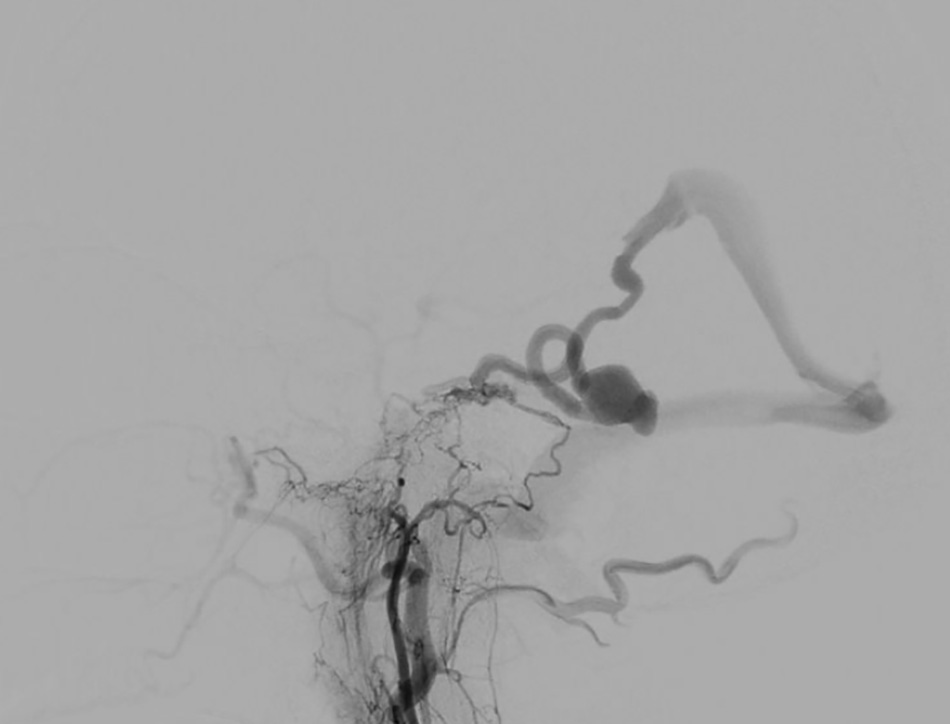

The brain vascular images of the patient were considered very “unusual,” showing a large venous aneurysm that had ruptured.

Interventional doctors thread the wire through the cerebral veins and begin deploying metal coils to occlude the aneurysm.